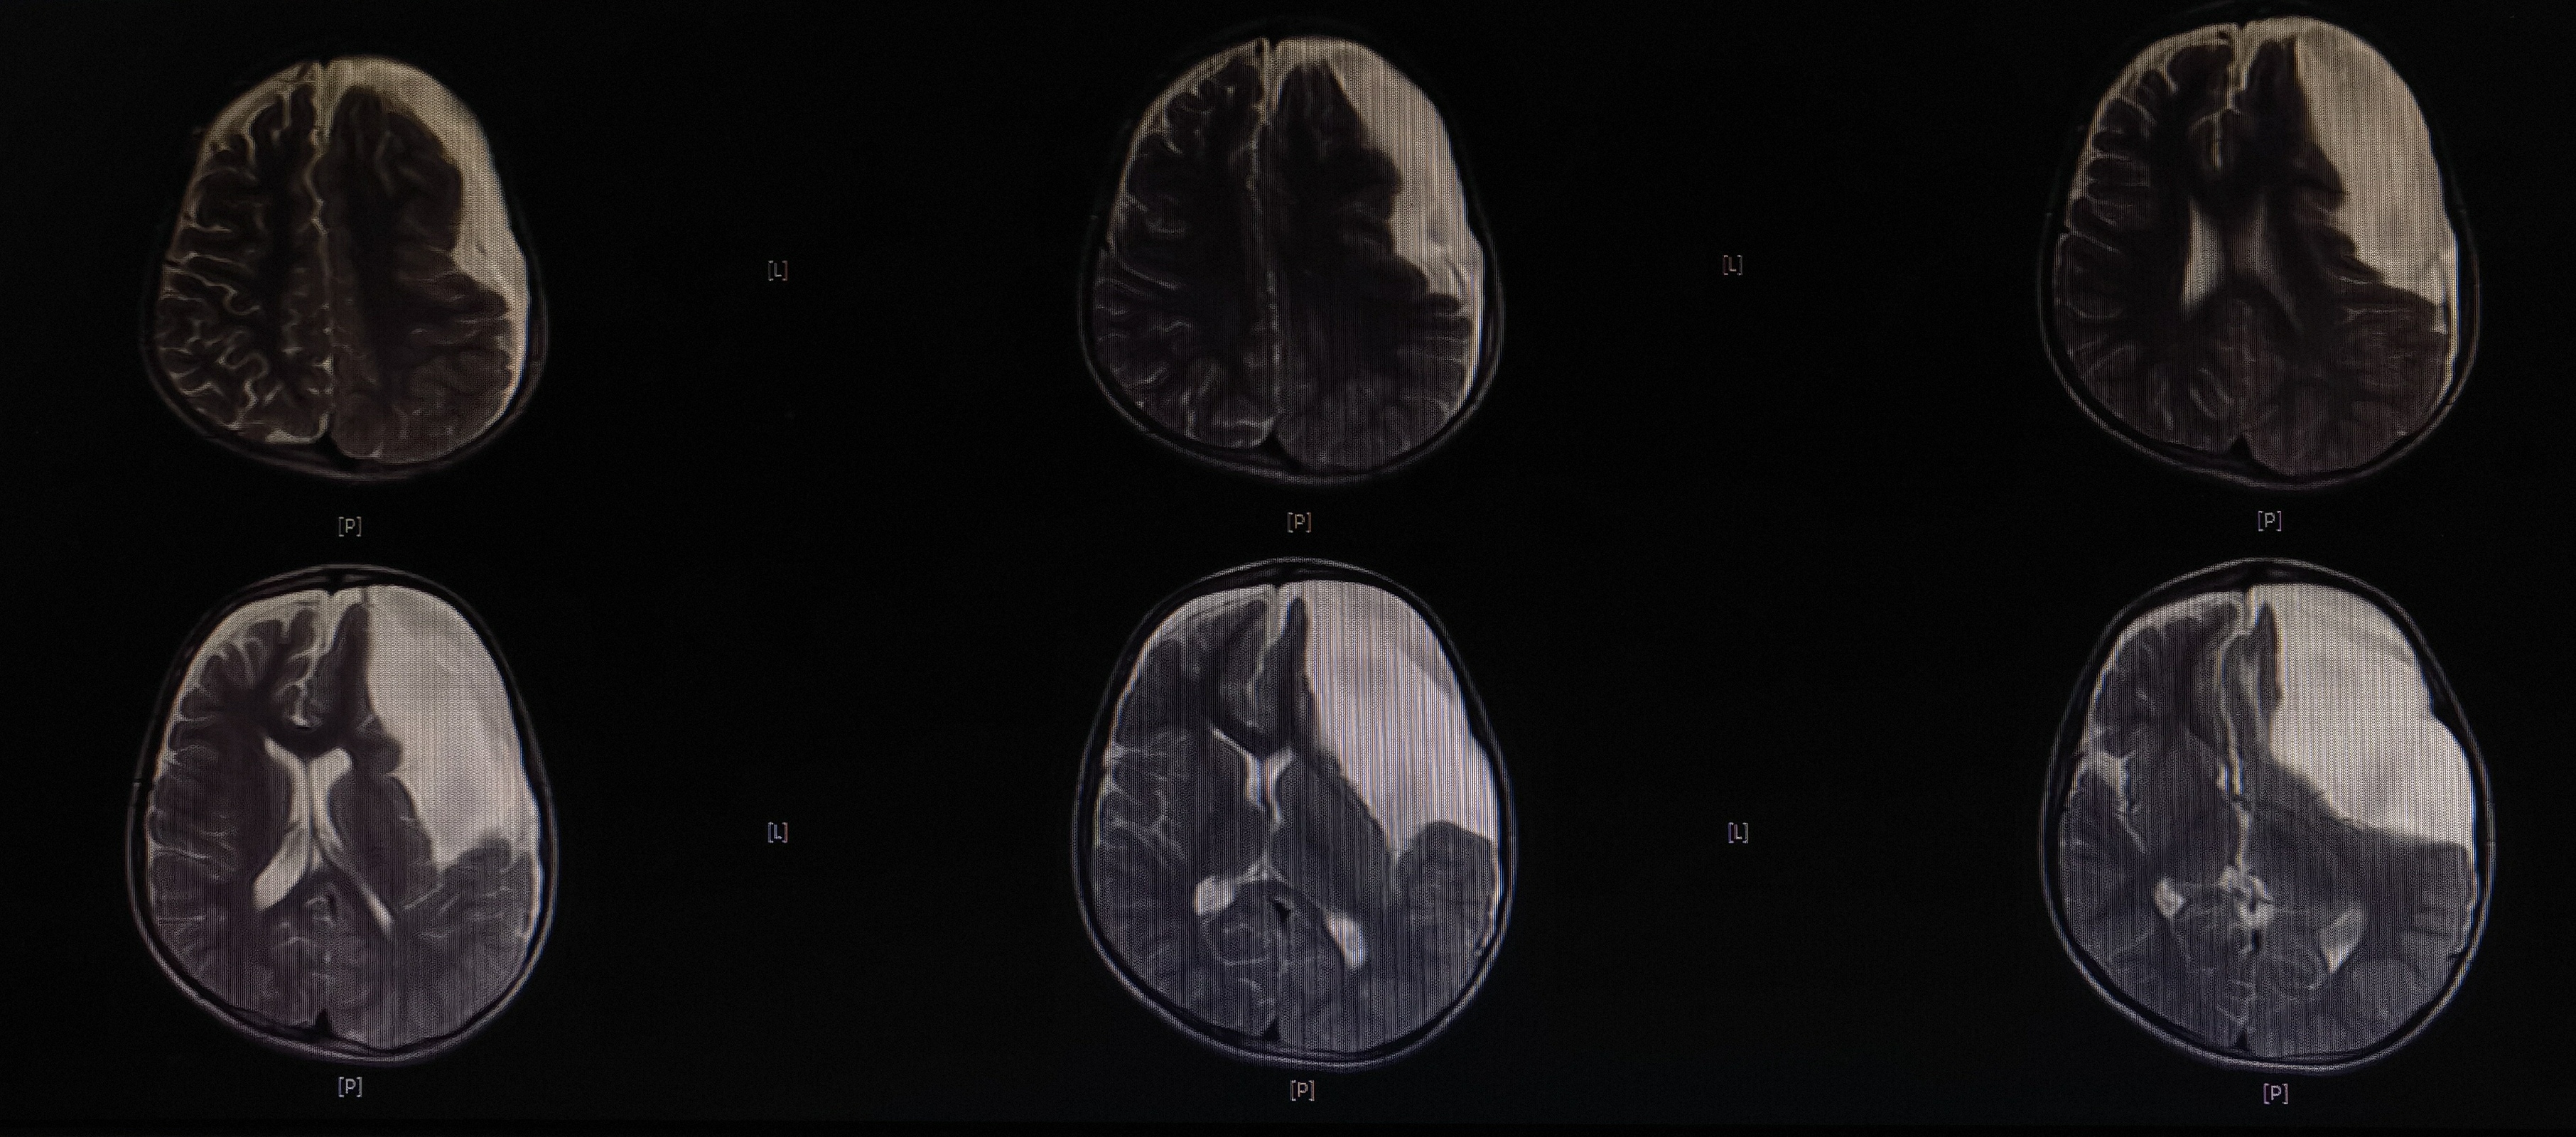

8岁男孩,以“头部外伤后头晕8天”入院,患儿8天前于3米高处坠落摔伤头部,伤后有昏迷史,当地医院CT提示左额颞巨大蛛网膜囊肿,破裂可能。患儿伤后感头晕,当地医院建议转至我院。我院完善头颅MR提示左额颞巨大蛛网膜囊肿,局部越过中线突入右侧镰旁挤压右额叶,左侧额颞岛叶明显受压,囊肿破裂可能。

术前MR